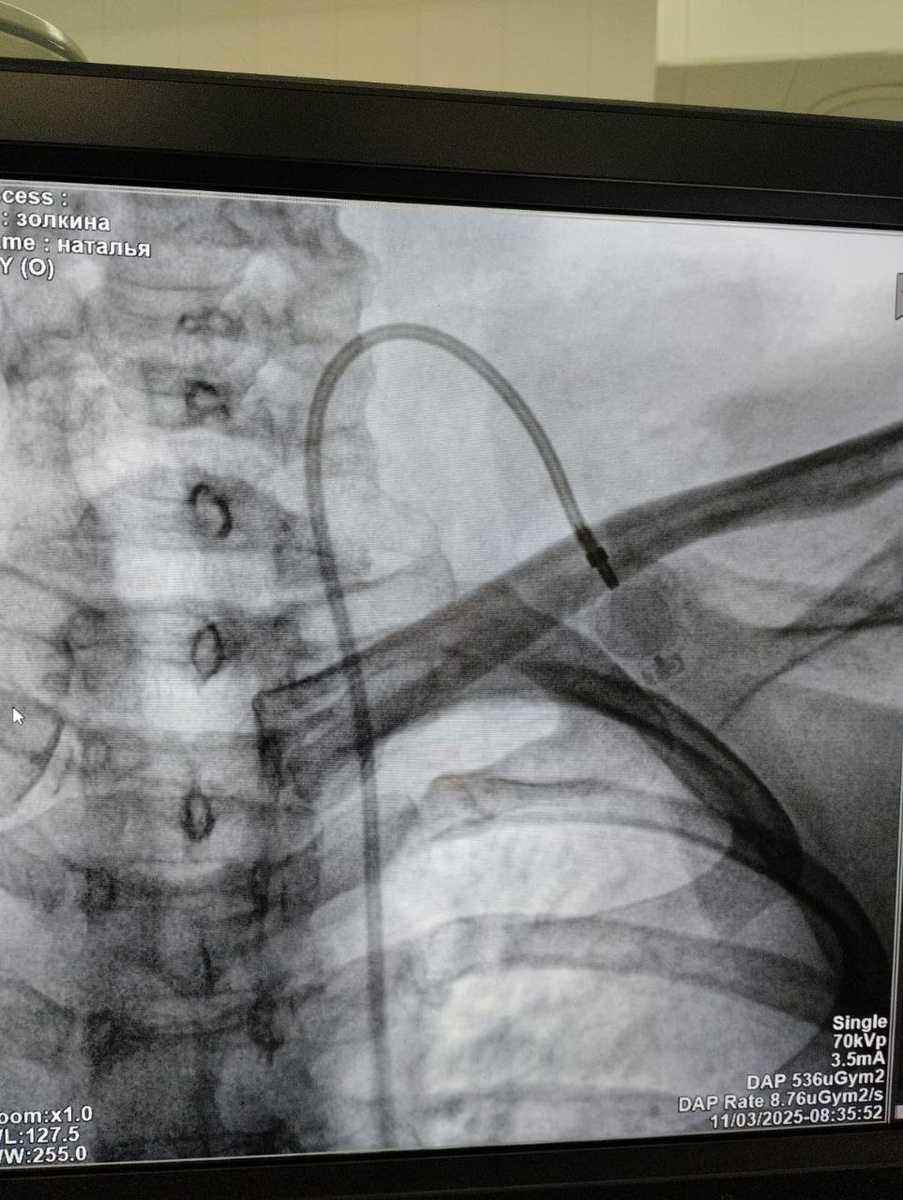

В Саратовском медицинском центре ФМБА России успешно внедрили современную методику подкожной имплантации порт-систем. Эти устройства предназначены для длительной и безопасной химиотерапии, парентерального питания и сложного лечения. Установку выполняет заведующий отделением сосудистой хирургии Виктор Анатольевич Егоров.

Это небольшой титановый резервуар с силиконовой мембраной, который имплантируют под кожу в подключичную область. К нему подводят катетер, который устанавливают в крупную магистральную вену. Система полностью скрыта под кожей, что позволяет пациентам вести привычный образ жизни — принимать душ, плавать и заниматься спортом.